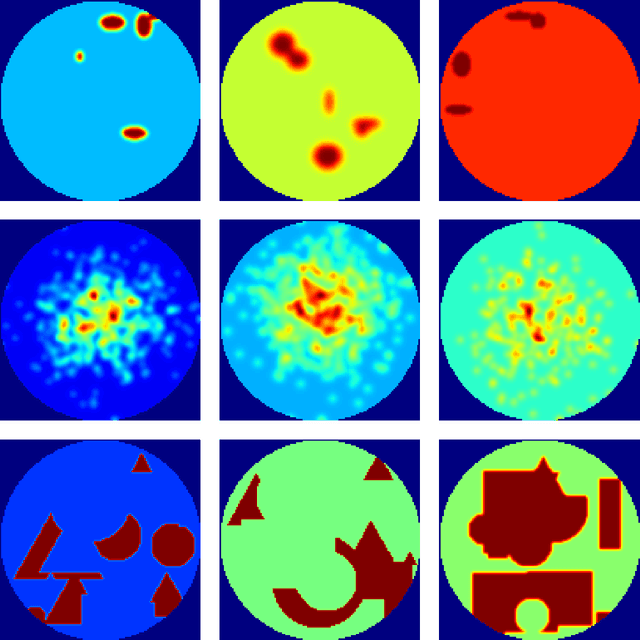

Abstract:In this paper, we present a novel method for tomographic image reconstruction in SPECT imaging with a low number of projections. Deep convolutional neural networks (CNN) are employed in the new reconstruction method. Projection data from software phantoms were used to train the CNN network. For evaluation of the efficacy of the proposed method, software phantoms and hardware phantoms based on the FOV SPECT system were used. The resulting tomographic images are compared to those produced by the "Maximum Likelihood Expectation Maximisation" (MLEM).